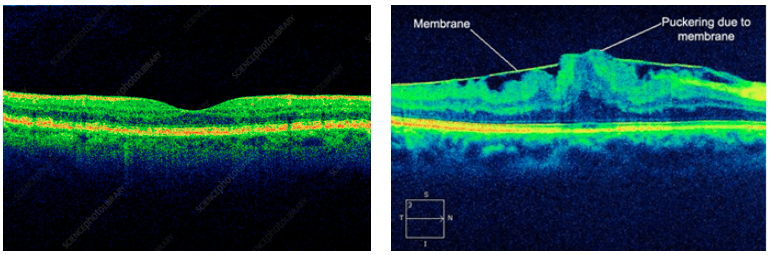

What is an epiretinal membrane?

An epiretinal membrane is a thin sheet of fibrous tissue that develops on the surface of the macular and can cause problems with central vision.

This is because this membrane can contract and cause distortion of the retina. As the macular is responsible for visually demanding tasks such as reading and sharp vision, epiretinal membranes can affect patients quite a lot.

What is the treatment for Epiretinal Membranes?

However, if worsening of vision occurs, surgery may be needed. There are no eye drops, medications or nutritional supplements to treat this. The surgery performed is similar to retinal detachment surgery and involves a vitrectomy.

- Length of time the epiretinal membrane has been present

- Degree of traction: or the amount of pulling on the macular by the membrane

- Cause of the epiretinal membrane: membranes caused by retinal detachment or retinal vascular problems do not do as well